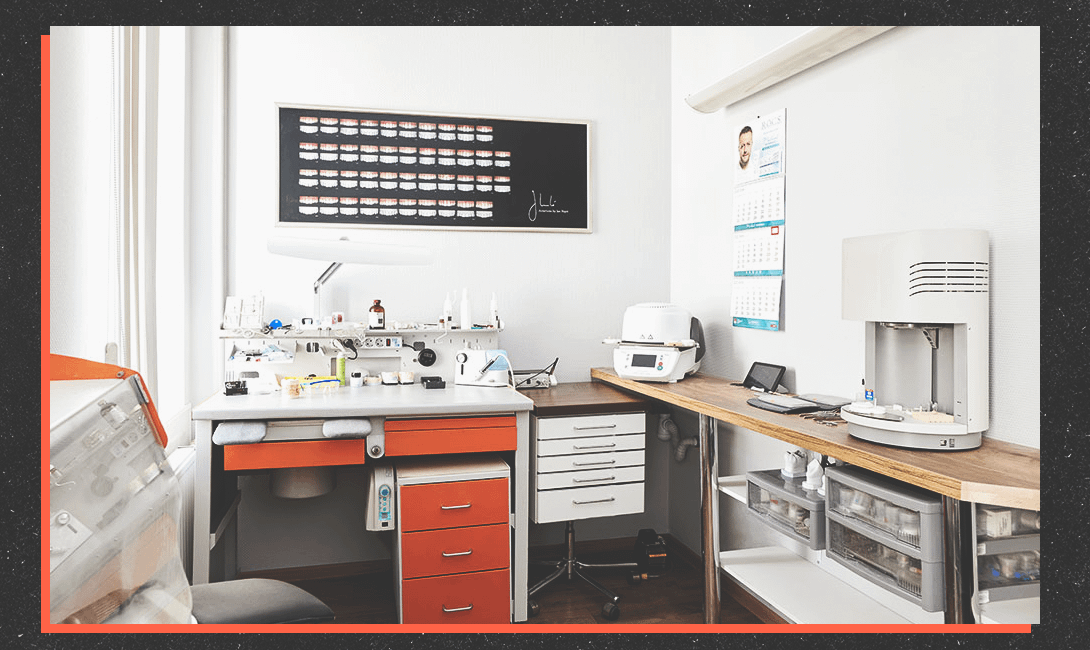

В каждом кабинете клиники есть стоматологический микроскоп для детального обследования. С его помощью удаётся увеличить место осмотра в 30 раз и выявить любую зубную болезнь ещё на стадии развития. Собственная зуботехническая лаборатория позволяет максимально быстро изготавливать различные индивидуальные конструкции – коронки, виниры, протезы и ортодонтические аппараты.